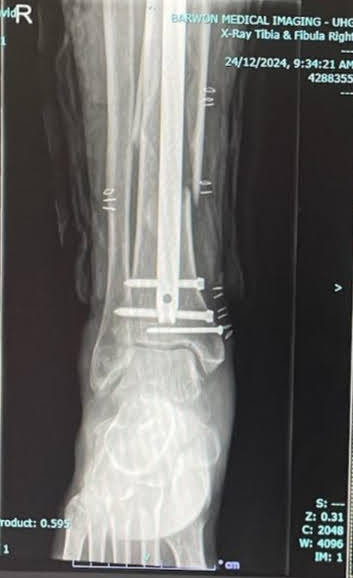

The outcome being Beak’s leg broken in 3 places, requiring some lengths of M8 all-thread and some 10G self tapers to put him back together.